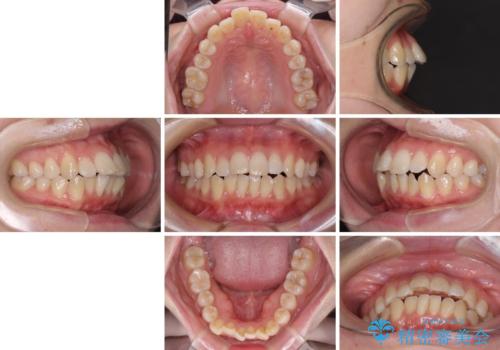

- 口元の突出感と口の閉じにくさを気にして来院された患者様です。

上下左右第一小臼歯4本を抜歯し、ワイヤー装置にて口元を引っ込めるよう矯正治療を行うこととしました。